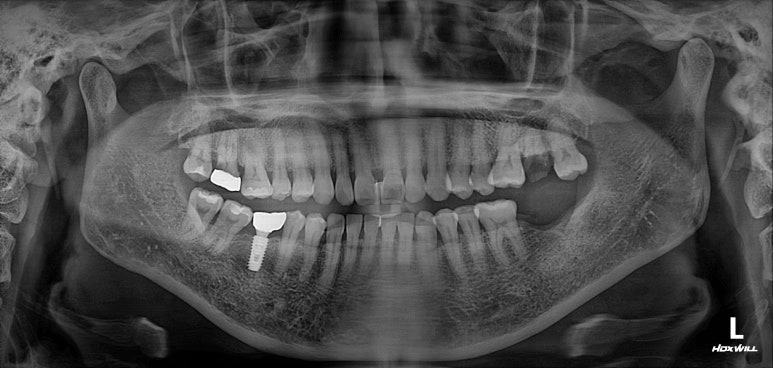

딱 봐도 치아가 조금 없는 것 같으시죠?

빨간색 동그라미로 표시된 곳에 치아가 없어요! 왼쪽 아래 두번째 어금니를 뽑으신 지 몇 년 지나신 상태였습니다.

노란색 동그라미로 표시된 치아는 뿌리만 있는 잔존치근 상태로, 살릴 수 없는 치아였어요.

그리고 마지막으로 파란색 동그라미로 표시된 치아는 기존 크라운 아래로 이차충치가 생겨서 신경치료가 필요한 상태!